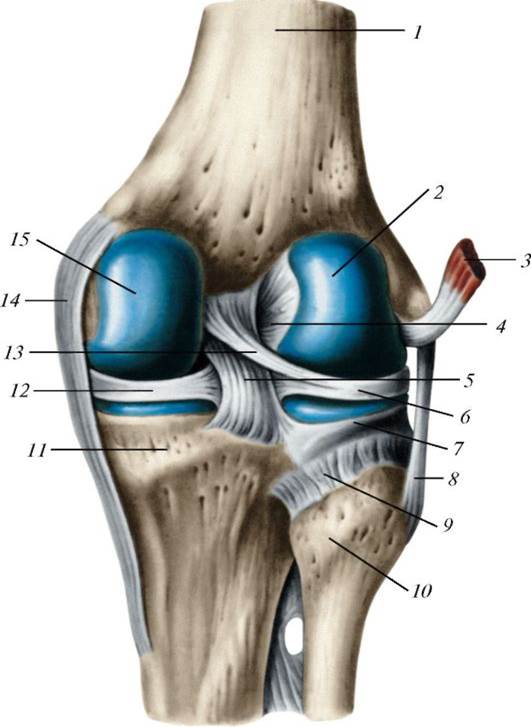

Анатомические изображения менисков и коленного сустава

Раздел: Иллюстрированные советы